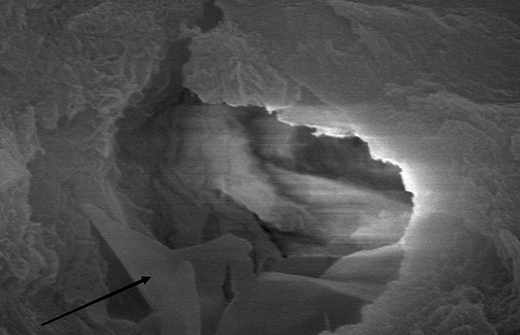

C-Root SP是預(yù)混合的、可即刻應(yīng)用的、可注射的、遇水凝固的硅酸鹽類生物活性陶瓷糊劑材料,主要成分為硅酸鍶、氧化鋯、磷酸鈣、氫氧化鈣,用于根管的密封和永久充填,適合單尖法、側(cè)壓法和熱牙膠法。 C-Root SP為世界口腔醫(yī)生提供一個“鍶生物陶瓷”的新選擇! >>>